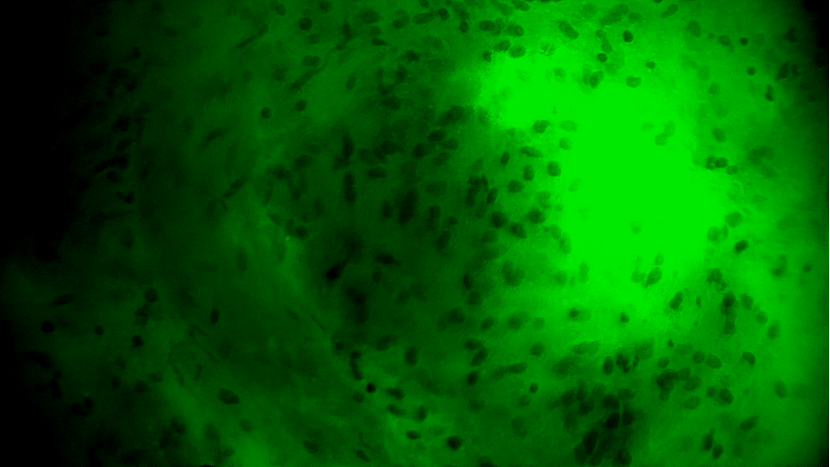

術(shù)中EndoSCell?細(xì)胞圖像如下:

腫瘤中心區(qū)域:細(xì)胞核異型性顯著,分布密集且不規(guī)則,陽性。

腫瘤邊緣區(qū)域:個(gè)別細(xì)胞核存在異型性,密度下降,分布不規(guī)則,陽性。

正常細(xì)胞組織:細(xì)胞核形態(tài)正常,分布均勻,陰性。